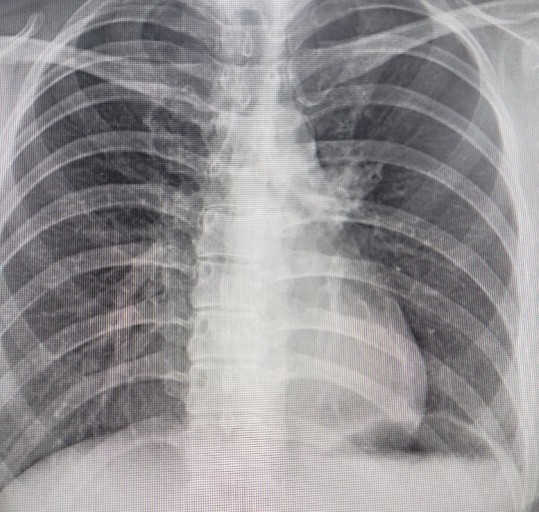

- 정기적인 건강 검진: 위와 같은 증상이 하나라도 나타나면 즉시 병원을 방문하여 흉부 X-ray, CT 촬영 등 검사를 받는 것이 중요합니다.

폐암은 암세포가 커지거나 주변 기관으로 전이되면서 다양한 증상을 유발합니다. 증상이 나타났을 때는 이미 어느 정도 진행된 경우가 많으므로, 아래 증상들을 주의 깊게 살펴봐야 합니다. 다음은 폐암 환자들이 흔히 겪는 10가지 주요 초기 증상입니다.

오늘은 많은 분들이 궁금해하는 폐암 초기 증상에 대해 이야기하려 합니다. 폐암은 한국인의 사망 원인 1위인 암으로, 초기에는 뚜렷한 증상이 없거나 감기와 비슷해 간과하기 쉽습니다.